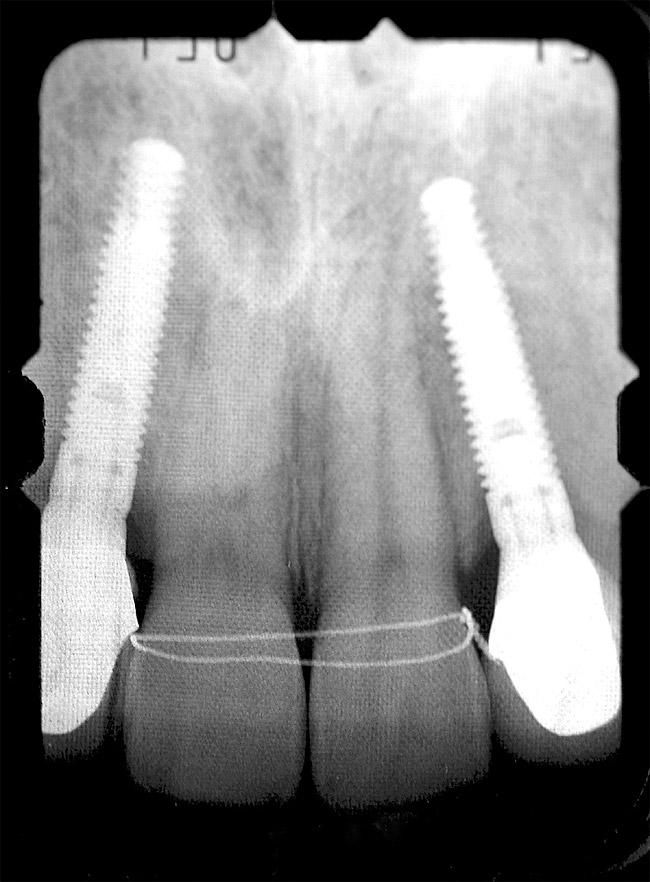

Periapical radiographs were taken to help determine the mesial-distal inclinations of the adjacent tooth roots (Figure 1). The radiographs revealed a serious issue, convergent roots for the right canine and right central, which eliminated that area as a potential implant-receptor site. The space between the left central and canine teeth was minimal, although the roots were relatively parallel. Clinical examination (manual palpation of the root eminences superiorly to the vestibule on the right side) confirmed the root convergence (Figure 2A). The flat, wide zone of the keratinized tissue and lack of interdental papilla was evident for the missing right lateral incisor. There was a marked difference in clinical appearance for the left lateral, which could impact the eventual plan of treatment (Figure 2B). Other significant clinical findings included bilateral facial bone concavities, which existed as a result of the congenitally missing tooth roots. As a diagnostic cue to the underlying bone topography, it is important to follow the demarcation between attached and unattached gingival tissue, and note the crestal width of the available keratinized tissue (Figure 2C).

Figure 1  Pretreatment radiographs revealed convergent roots for the right canine and right central.

Figure 1